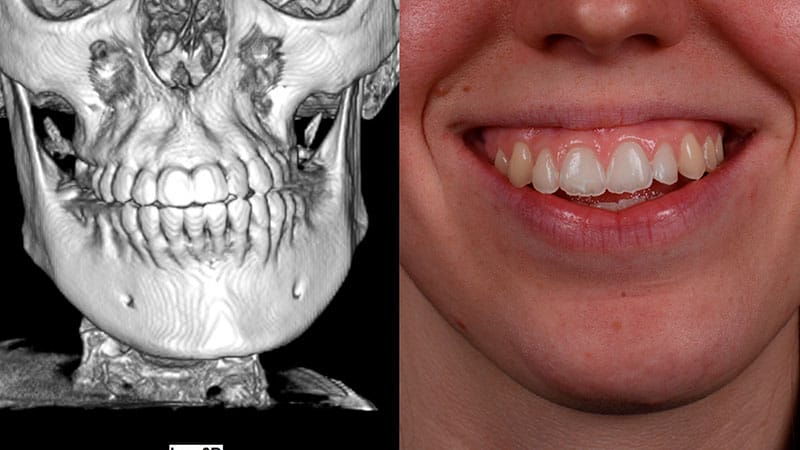

“Mi sonrisa refleja ahora confianza y armonía”

El tratamiento incluyó la reconstrucción ósea y gingival mediante cirugía regenerativa, seguida de una preparación ortodóntica con nuevos brackets para alinear correctamente los dientes. Posteriormente, se realizó una cirugía ortognática para reposicionar los huesos maxilares. Seis meses después, Sofía presentó una oclusión adecuada, mejoras estéticas faciales significativas y una mordida funcional.

¿En qué consiste el diagnóstico inicial en ortodoncia quirúrgica?El diagnóstico inicial incluye una serie de pruebas diagnósticas para la evaluación exhaustiva de dientes, encías, bases óseas y proporciones faciales. Esto permite identificar problemas funcionales y estéticos y definir un plan personalizado para el tratamiento.